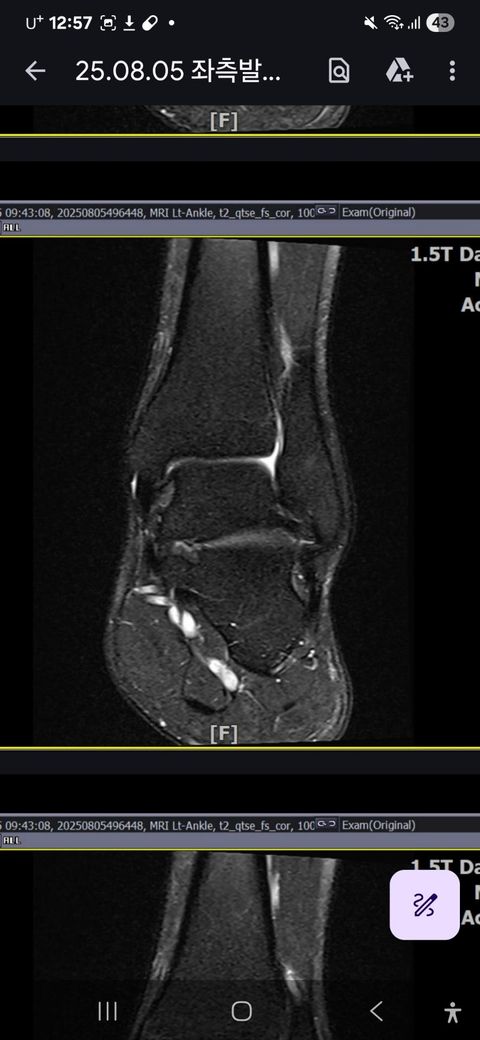

발목인대 상태 질문드립니다. (mri사진 첨부)

그런데 다친 지 2주 뒤부터 발목이 쑤시듯 아파 병원에서 초음파 검사를 했고, 전거비인대(ATFL) 2도 염좌 진단을 받았습니다. 이후 약 6주 동안 주 1회씩 충격파, 물리치료, 도수치료 등을 받았습니다. (고정치료는 시기가 늦었다며 진행하지 않았습니다.)

그래도 통증이 남아 8월 5일에 MRI를 촬영했는데, 병원에서는 “인대는 이어져 있고, 이 정도면 재활운동으로 호전될 것”이라는 설명을 들었습니다.

MRI 상 전거비인대와 발목 상태가 정말 회복 단계인지, 아니면 만성으로 넘어가는 건 아닌지 전문가분들의

의견을 듣고 싶습니다.

• 1번 째 사진

올려주신 mri를 보면 전거비인대는 연속성이 유지되고 있고 파열이나 큰 손상 흔적은 없어 재활로 회복 가능한 상태로 보입니다 다만 3개월 가까이 활동 시 통증과 미열감이 남아 있는 것은 조직 회복이 아직 완전히 끝나지 않았거나 주변 연부조직 관절 움직임 제한 등으로 인한 과민 반응일 수 있습니다.

초음파와 비교하면 mri 상으로 인대 연속성이 확인되므로 심각한 악화나 재파열은 아닌 것으로 판단됩니다